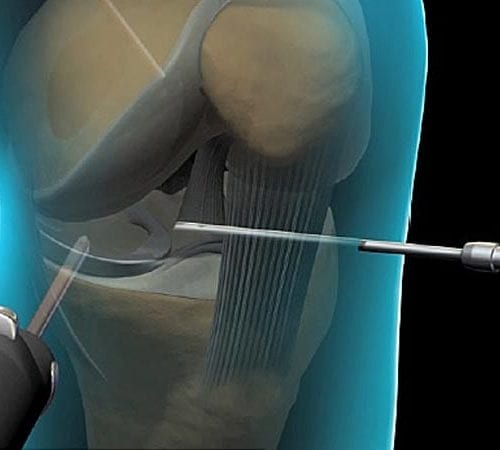

Menisküs Yırtığı ve Tedavisi